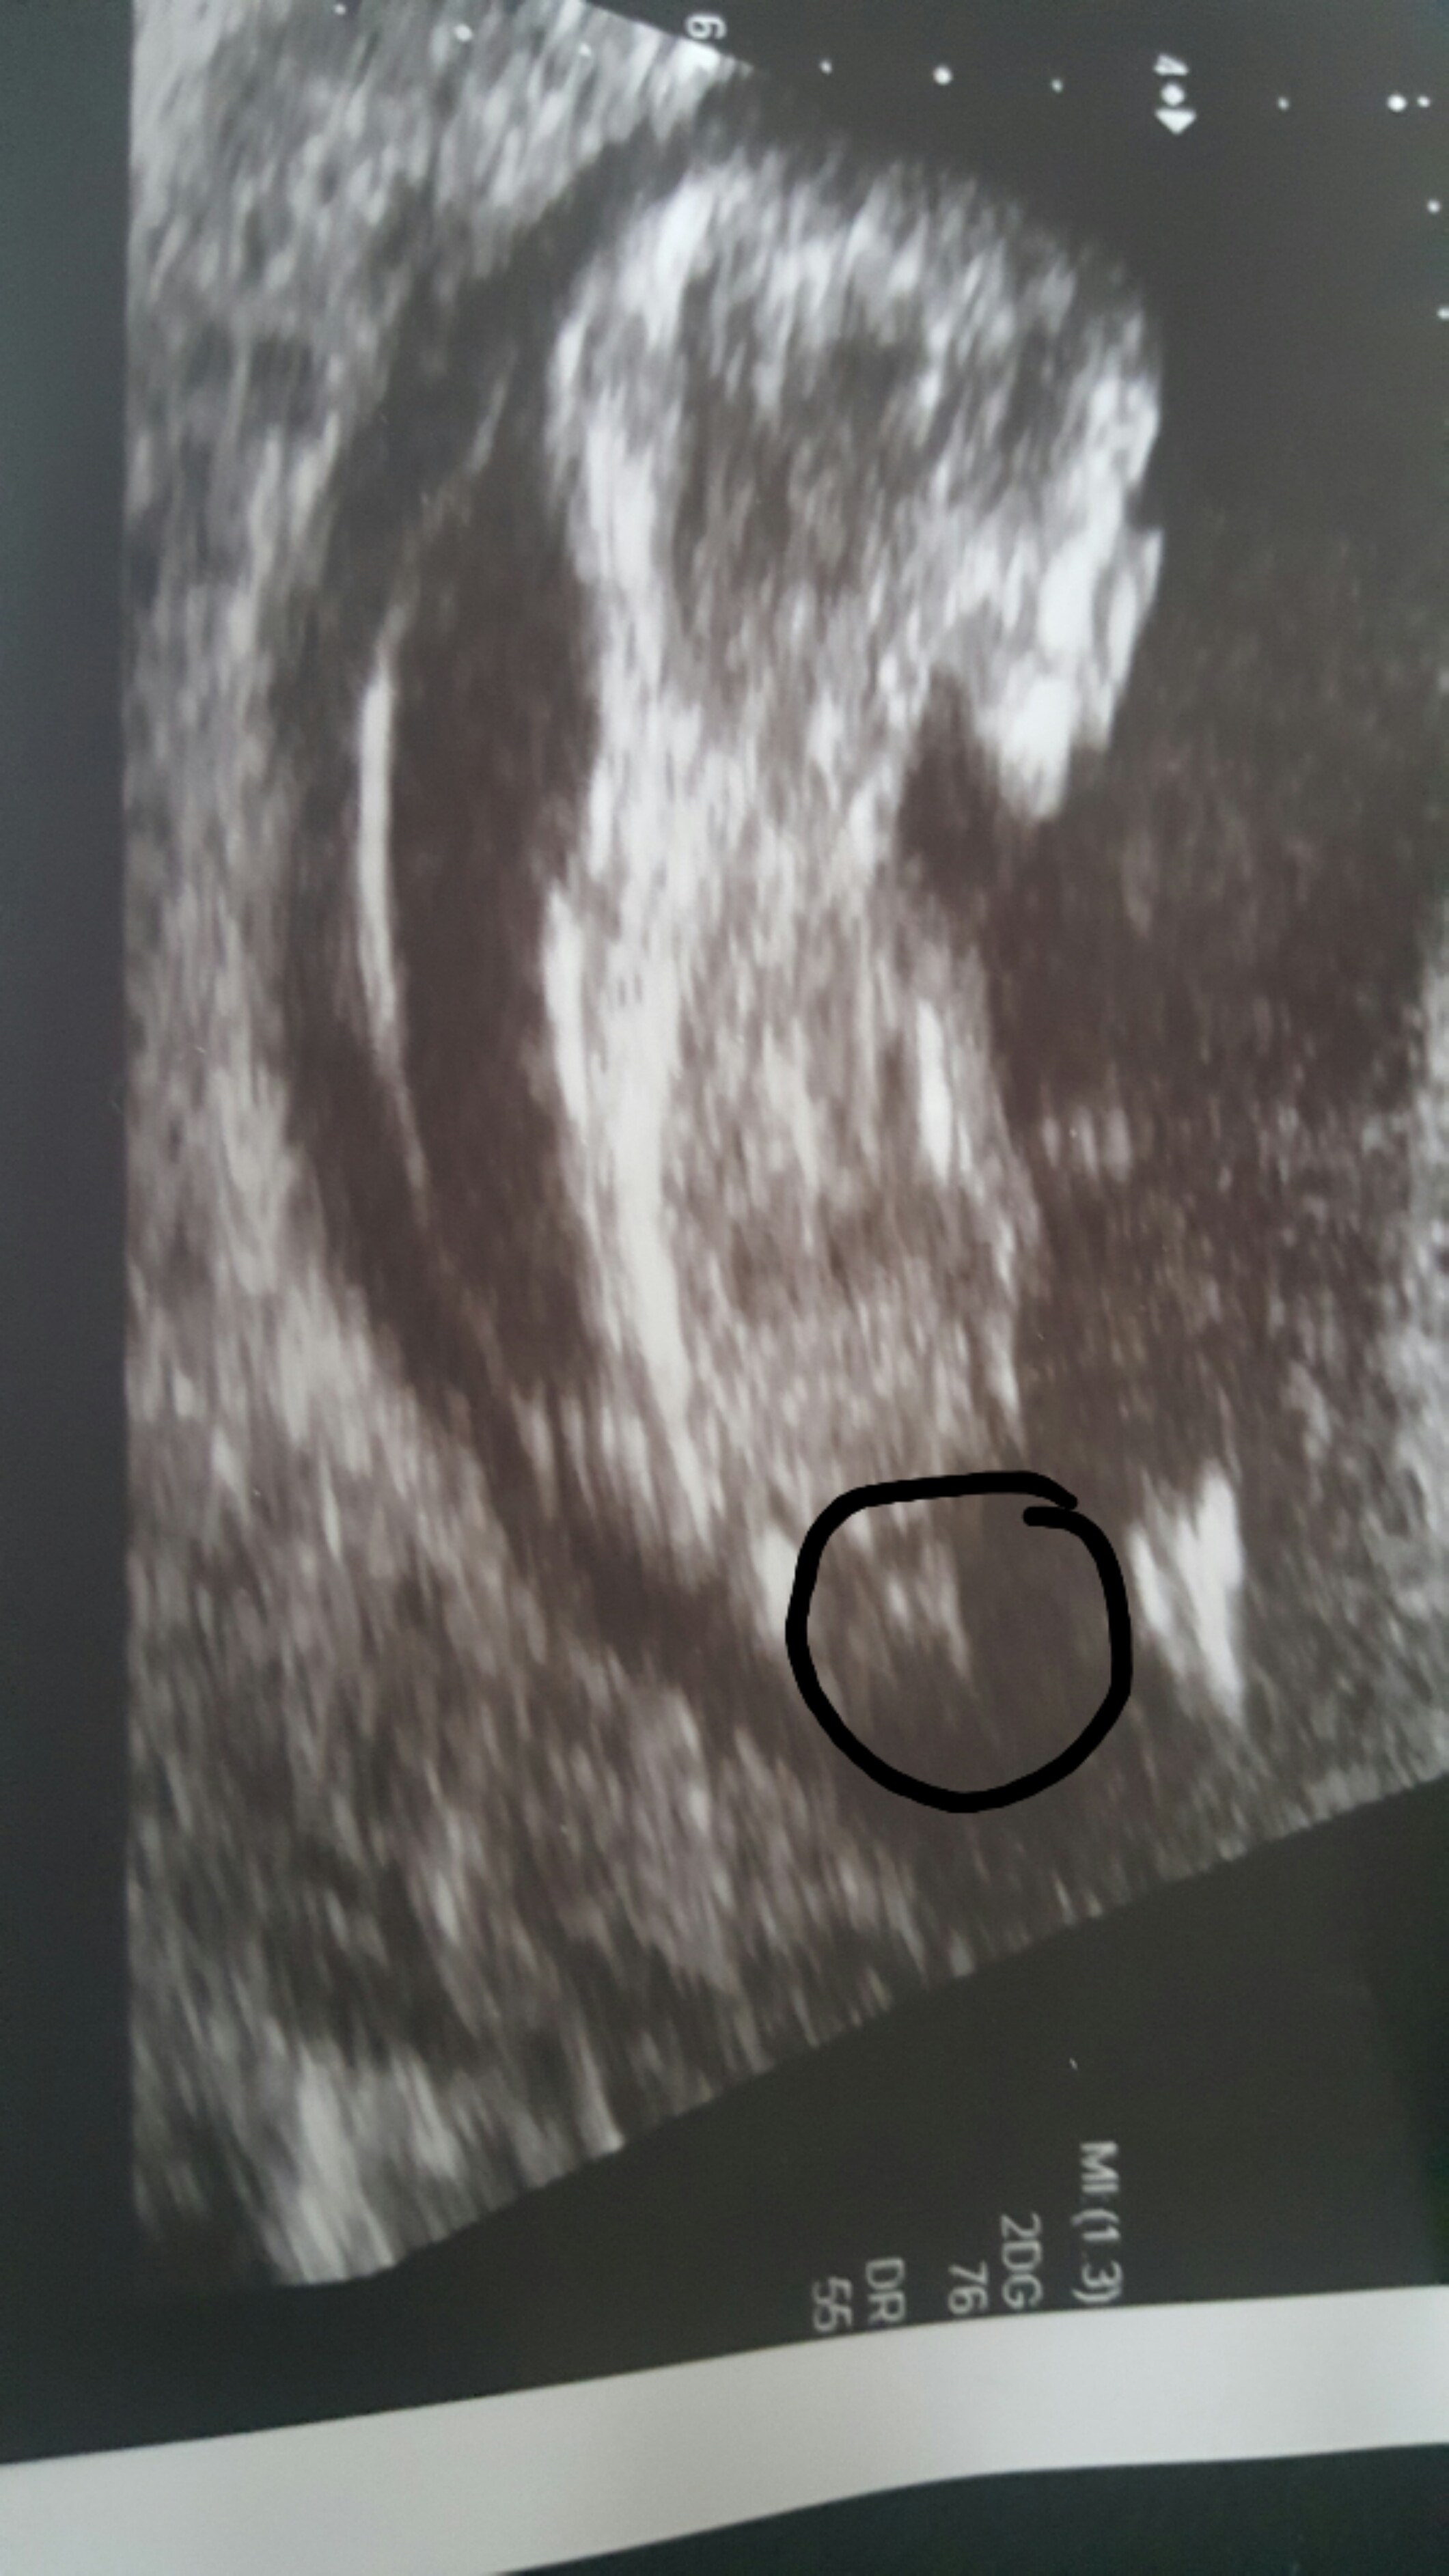

Hi all got my scan done yesterday 12 weeks 4 days. Would love to know what people think before my next scan tiaAttachment 30691